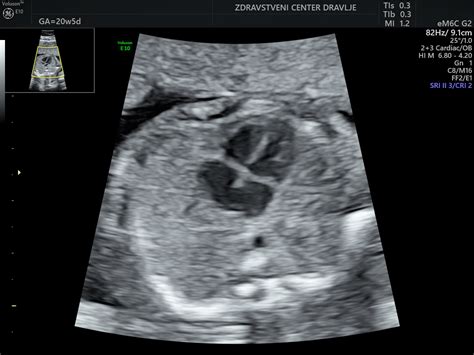

Specializirani fetalni ehokardiolog lahko z veliko natančnostjo, kar okoli 95%, odkrije vse pomembne srčne napake. Ta napredna preiskava se običajno izvede med 18. in 24. tednom nosečnosti, v drugem trimesečju, ko je srce ploda dovolj razvito za podrobno oceno zgradbe in funkcije. S pomočjo ultrazvočnih valov, ki se odbijajo od srca nerojenega otroka, lahko ocenimo srčne strukture, prekatne in preddvorne pretine, zaklopke ter srčni ritem.

Pregled srca je del rutinskega pregleda morfologije ploda med 20. in 23. tednom nosečnosti, ki ga opravljajo ginekologi. Ta pregled sam po sebi odkrije približno 40% pomembnih srčnih napak. Vendar pa se lahko z usmerjeno ultrazvočno preiskavo plodovega srca s strani specialista delež odkritih napak poveča na več kot 95%.

Predporodna skrb vključuje skrbno spremljanje zdravja matere in ploda. V primeru suma na srčno napako pri plodu ali ob prisotnosti dejavnikov tveganja, se lahko izvedejo dodatni presejalni testi ali preiskave, kot je fetalni ultrazvok srca. V ZC Dravlje lahko opravite specializirani ultrazvok srca pri plodu pri specialistu fetalno ehokardiografije, doc. Samu Veselu. Za naročilo na pregled lahko pokličete na 051 336 847 ali se obrnete preko spletnega obrazca.